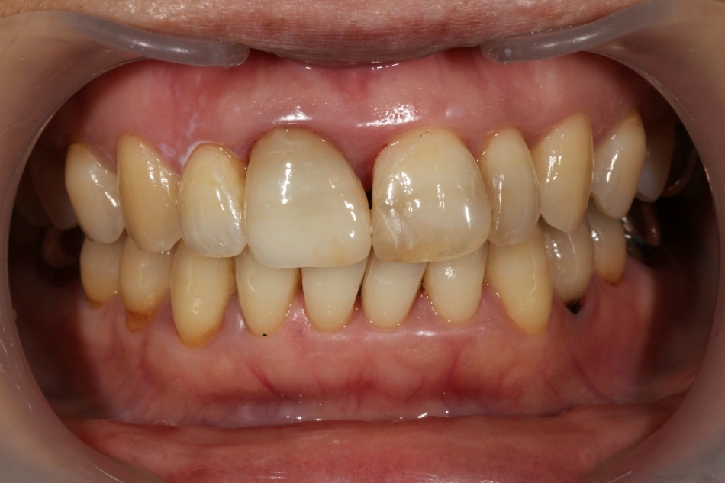

オールセラミックス修復

担当歯科医師:丸林浩太郎

2013年5月11日千葉市中央区 K.N様 上顎12番 オールセラミッククラウン修復